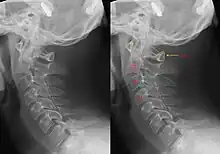

Hangman's fracture is the name given to a fracture of both pedicles (partes interarticulares) of the axis vertebra (C2) in the neck, and associated with a defect in the space between C2 and C3.[1]

It occurs as a result of a combination of hyperextension, flexion and compression in the neck.[1] There are generally three types.[1] Types I and II are typically managed with a hard collar, whereas surgically fusing C2 and C3 is required for type III.[1]

Although a hangman's fracture is unstable, survival from this fracture is relatively common, as the fracture itself tends to expand the spinal canal at the C2 level. It is not unusual for patients to walk in for treatment and have such a fracture discovered on X-rays. Only if the force of the injury is severe enough that the vertebral body of C2 is severely subluxed from C3 does the spinal cord become crushed, usually between the vertebral body of C3 and the posterior elements of C1 and C2.